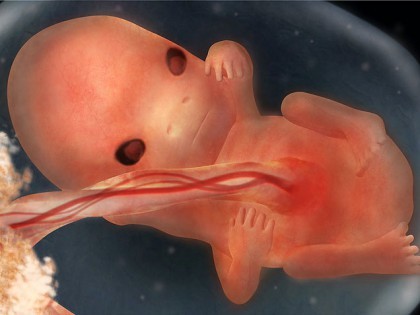

Foetus 9 Weken Zwanger Mama Love